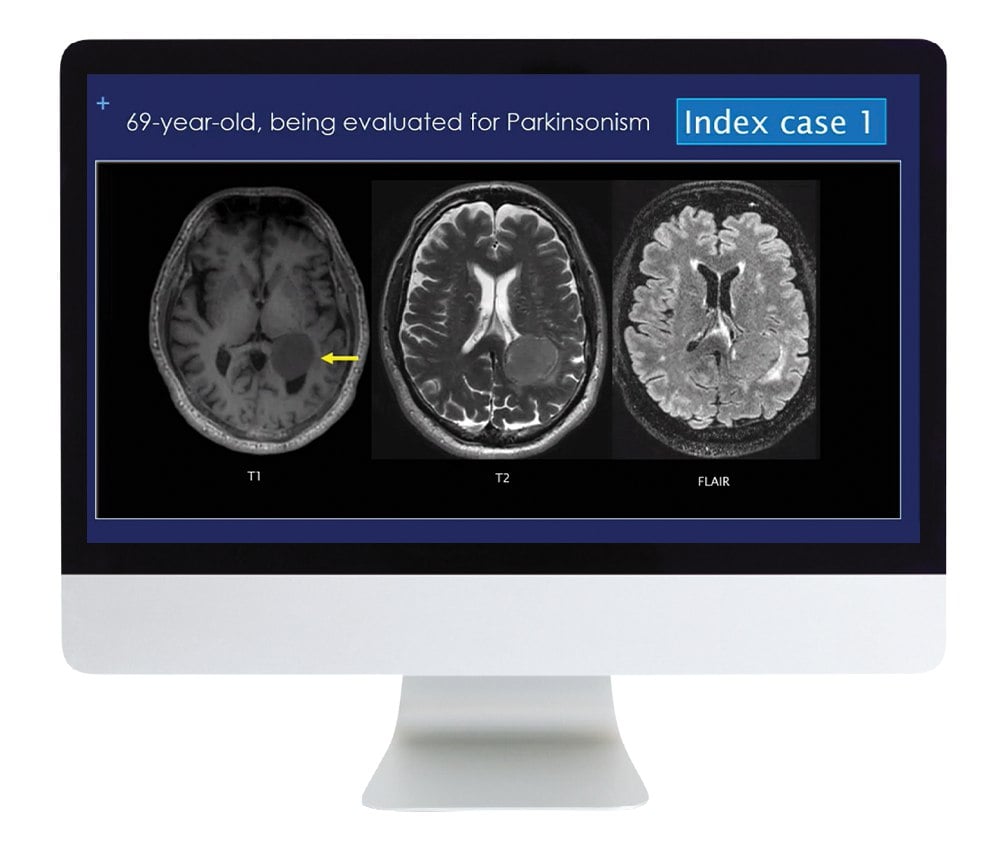

Case Review of Neuroradiology

Case Review of Neuroradiology

Case Review of Neuroradiology Tailored for neuroradiologists, this comprehensive course empowers you to elevate your diagnostic expertise and accuracy in navigating a wide spectrum of neuroradiology scenarios. Develop the proficiency to recognize crucial imaging indicators and apply your clinical insights to achieve advanced and precise diagnoses. With a specialized focus on neuroradiology, delve into unique and prominent characteristics, hone your differential diagnosis skills, and arm yourself with the tools needed to make knowledgeable and impactful management decisions in a range of complex clinical scenarios.

- Develop differential diagnoses for conditions in neuroradiology.

- Recognize imaging features that are highly characteristic of a specific diagnosis or diagnostic set in neuroradiology.

- Recognize the imaging and clinical features that allow for refinement of differential diagnosis, allowing for a more specific diagnosis.